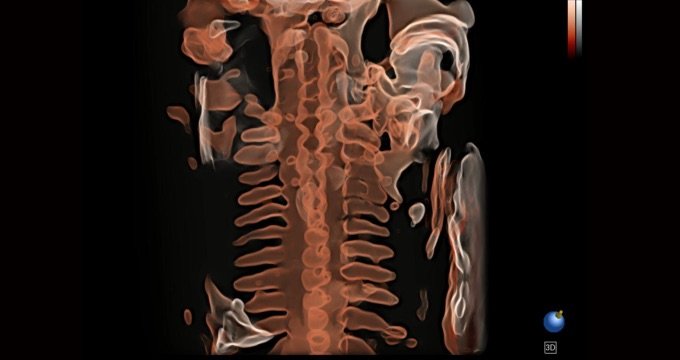

S-Live Silhouette

Durch den Einsatz einer virtuellen Lichtquelle und des Schattierungseffekts sieht S-Live Silhouette durch die Oberfläche hindurch und bildet die Umrisse von Knochen, Organen, Hohlräumen, Gefäßwänden und anderen inneren Strukturen scharf ab. Diese Funktion eignet sich hervorragend zur Erkennung der normalen Anatomie und zur Diagnose komplexer angeborener Fehlbildungen.